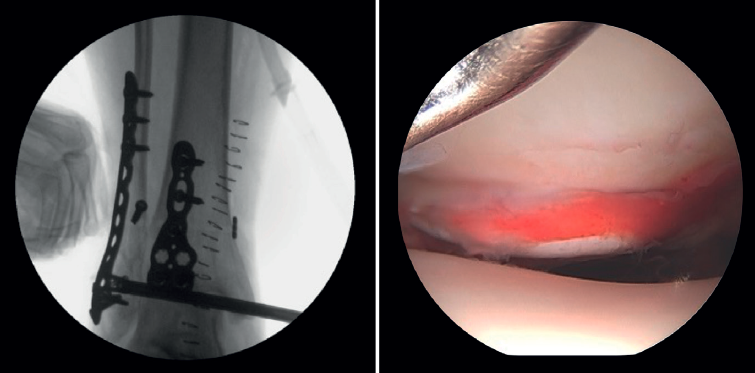

- Assessment of reduction of the posterior malleolus: arthroscopy can be used to verify reduction of the posterior malleolus(5)(Figure 2).

Arthroscopy assists ORIF in evaluating the congruence of the joint surface. It is especially useful for reduction of the medial malleolus. The malreduction rate in medial malleolus fractures is 22.2-32.6%(15,16). Initial arthroscopy allows us to determine whether tibial malleolus reduction can be performed in an open or closed manner. In cases with significant displacement, open synthesis is chosen, always maintaining arthroscopic control during the procedure to ensure precise reduction and avoid rotation of the distal fragment (Figure 4).

Xie showed that stabilization of the syndesmosis with a dynamic fixation system offers equivalent functional results and fewer complications compared to screw fixation(28). AAORIF allows the evaluation of joint congruency after anatomical reduction of both the posterior and anterior syndesmosis. It also allows assessment of the overcorrection that can result from over-compression of the tibiofibular mortise, which has been shown to be highly arthrogenic(29). During reduction of the syndesmosis, help is provided by a palpation probe which we should be able to insert once the syndesmosis has been fixed.